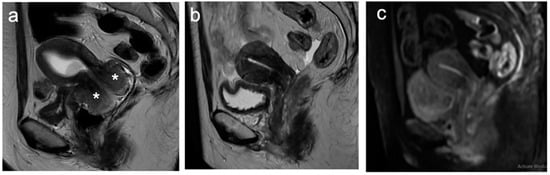

| Stage II | The cervical carcinoma invades beyond the uterus, but has not extended onto the lower third of the vagina or to the pelvic wall |

| IIA | Involvement limited to the upper two-thirds of the vagina without parametrial invasion |

| IIA1 | Invasive carcinoma <4 cm in greatest dimension |

| IIA2 | Invasive carcinoma 4 cm in greatest dimension |